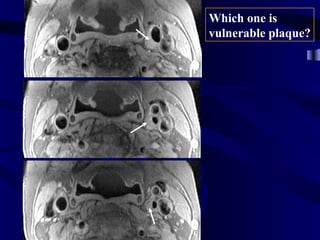

Morphology vs. Activity Imaging

plaque

May Appear Similar

in

IVUS OCT MRI

w/o CM

Morphology

Show Different

Activity

Thermography, Spectroscopy,

immunoscientigraphy, MRI with

targeted contrast media…

Which one is

vulnerable plaque?

High Level of Sensitivity and Specificity Needed

• Knowing the high prevalence of

atherosclerosis in apparently healthy

population, in order to accurately detect

vulnerable plaques and vulnerable patients,

it is imperative to obtain information about

both structure and activity of plaque

assuring minimum false positive and false

negative results.